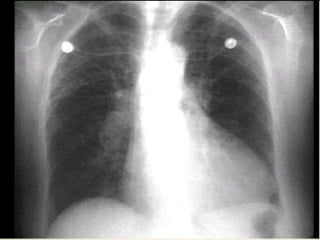

CASO CLÍNICO: Femenina de 78 años con edema agudo pulmonar y PA 170/120 mmHg, FC 120 por minuto, S3 apical, estertores crepitantes. ECG: Eje -30o., Voltaje QRS aumentado en derivaciones V5-V6. RX: Cardiomegalia III/IV y HVCP III/IV ECO: Trastorno de relajación y FE 42%

DIAGNÓSTICO: HAS E-2 primaria, riesgo C por cifras y daño a órgano blanco (Cardiopatía hipertensiva) Insuficiencia Cardiaca por Disfunción mixta: Sistólica y Diastólica,  Clase IV NYHA,  Tres Criterios mayores de Framingham

ESTUDIOS DIAGNÓSTICOS: ECGPA Tórax M.A.P.A. Ecocardiograma

CASO CLÍNICO: Femeninade 78 años con edema agudo pulmonar y PA 170/120 mmHg, FC 120 por minuto, S3 apical, estertores crepitantes. ECG: Eje -30o., Voltaje QRS aumentado en derivaciones V5-V6. RX: Cardiomegalia III/IV y HVCP III/IV ECO: Trastorno de relajación y FE 42%

DIAGNÓSTICO: HAS E-2primaria, riesgo C por cifras y daño a órgano blanco (Cardiopatía hipertensiva) Insuficiencia Cardiaca por Disfunción mixta: Sistólica y Diastólica, Clase IV NYHA, Tres Criterios mayores de Framingham